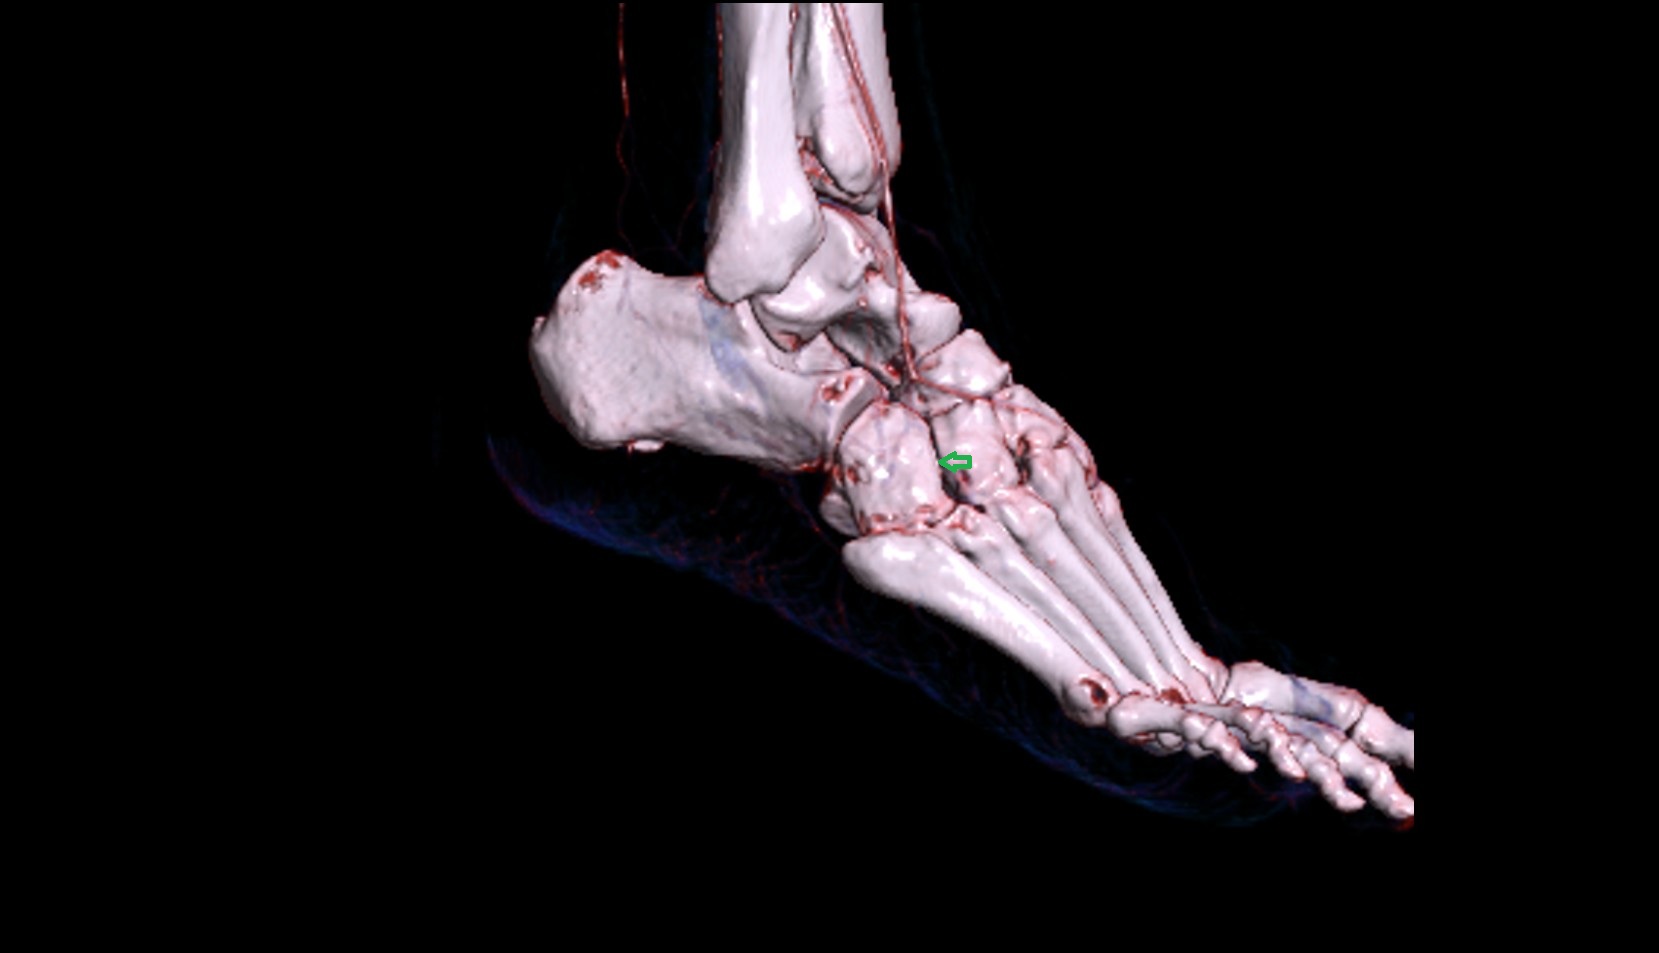

- Talus

- Head of talus

- Body of talus

- Neck of talus

- Calcaneus

- Anterior process of calcaneus

- Sustentaculum tali

- Tuberosity of navicular bone

- Cuboid

- Ankle joint

- Talocalcaneal joint

- Talocalcaneonavicular joint

- Calcaneocuboid joint

- Cuneocuboid Joint

- Lateral cuneiform bone

- Medial cuneiform bone

- Intermediate cuneiform bone

- Navicular bone

- First metatarsal bone

- Second metatarsal bone

- Third metatarsal bone

- Fourth metatarsal bone

- Fifth metatarsal bone